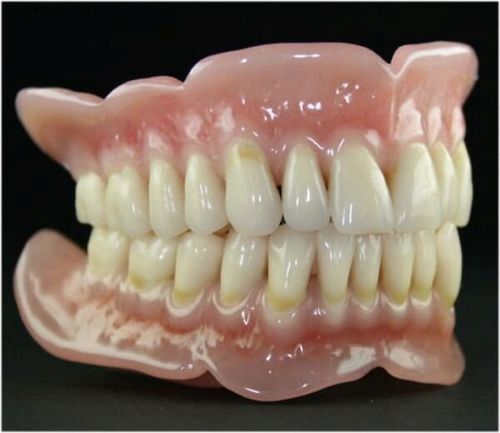

- при носінні протезів може виникнути на матеріал, який використовується для виготовлення даної конструкції .

Основна причина контактної форми стоматиту - це тривалої вплив матеріалів або препаратів, на слизову.

Як подразника може виступати протез, засіб для його фіксації, засіб для догляду за порожниною рота. На відміну від медикаментозного, має чітку локалізацію, розвиваючись лише на слизовій оболонці рота.

Для початку визначається наявність провокуючих чинників: спадковості, запалень порожнини рота або ЛОР-органів, інших захворювань. При носінні протезів, визначається їх термін використання і якість матеріалу.

- проби провокаційного характеру, з попеременной заміною матеріалів для протеза і стоматологічних засобів,